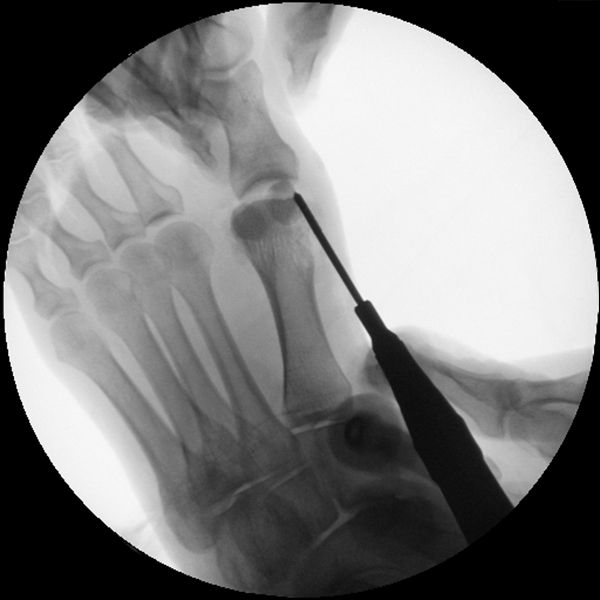

Der von Isham/Reverdin beschriebenen minimal invasiven Technik zur Korrektur einer Hallux valgus Deformität liegen 4 Operationsschritte zu Grunde:

1. Abtragung der Exostose am Köpfchen des 1. Mittelfußknochens

2. Subcapitale intraartikuläre Osteotomie

3. Laterales Release

4. Akin Osteotomie der Großzehengrundphalanx

Die Folge der Operationsschritte sollte strikt von 1. - 4. erfolgen, da ansonsten die mediale Closing Wedge Osteotomie bei vorzeitigem lateralem Release und/oder Akin Osteotomie nicht geschlossen werden kann. Nach der von Isham beschriebenen Originaltechnik finden Implantate keine Anwendung, zur Sicherung und besseren Fixation können osteosynthetische Verfahren angewandt werden (siehe auch Fehler, Gefahren und Komplikationen).